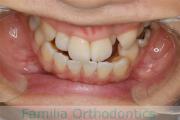

No.22V-449

- 主な症状:

- 上顎前突

- その他の症状:

- 叢生

- 年齢:

- 14歳

- 性別:

- 男性

- 抜歯部位

- 上:

- 44

- 下:

- 8448

- 主な使用装置:

- FEA

- 治療にかかった費用:

- 87万円

歯並びをきれいにしたいということで来院されました。上下左右から小臼歯を抜歯して、マルチブラケット法を行っています。2年弱、25回程度の通院が必要でした。

かなり強い叢生(でこぼこ、凹凸、ガタガタ)ですので、保定をしっかりしないと後戻りのリスクがあります。

- ≫治療前

-